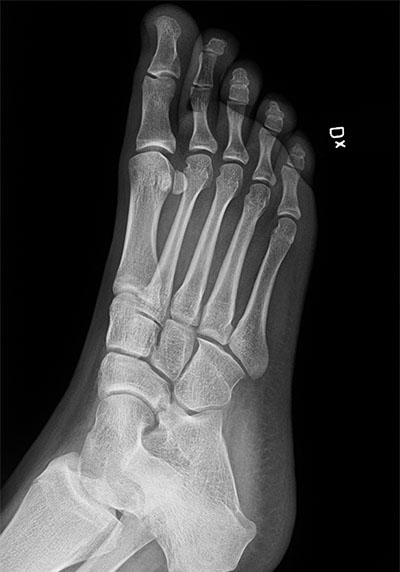

PLATT FOT BOT

Bakgrund: Platt Fot Bot eller HyProCure (Hyper pronation cure) är en metod som innebär att en titanskruv (stent) skruvas in i sinus tarsi på patienter med pes plonovalgus.

vid plattfot (se bild ovan). Genom att välja storlek på skruv kan man enkelt bestämma hur mycket fotvalv man vill ha. Metoden anges inte bara bota plattfot utan även besvär från höft, knä och rygg!

Resultat: Metoden marknadsförs intensivt på nätet och med hjälp av s.k. influencers. Trots att filosofin bakom metoden är biomekaniskt och biologiskt felaktig och trots att det helt saknas vetenskaplig dokumentation (om man undantar sju publikationer av metodens uppfinnare, varav flertalet avser försök på avlidna) har metoden fått viss spridning även i Sverige. Det finns ingen oberoende vetenskaplig granskning och inga långtidsuppföljningar. Däremot finns missnöjda patienter som inte bara fått skruvar inskruvade utan ofta även utskruvade.

Hypotes: genom att göra en artroris (skruva in en titanskruv mellan talus och calcaneus) kan fotens längsgående fotvalv återställas